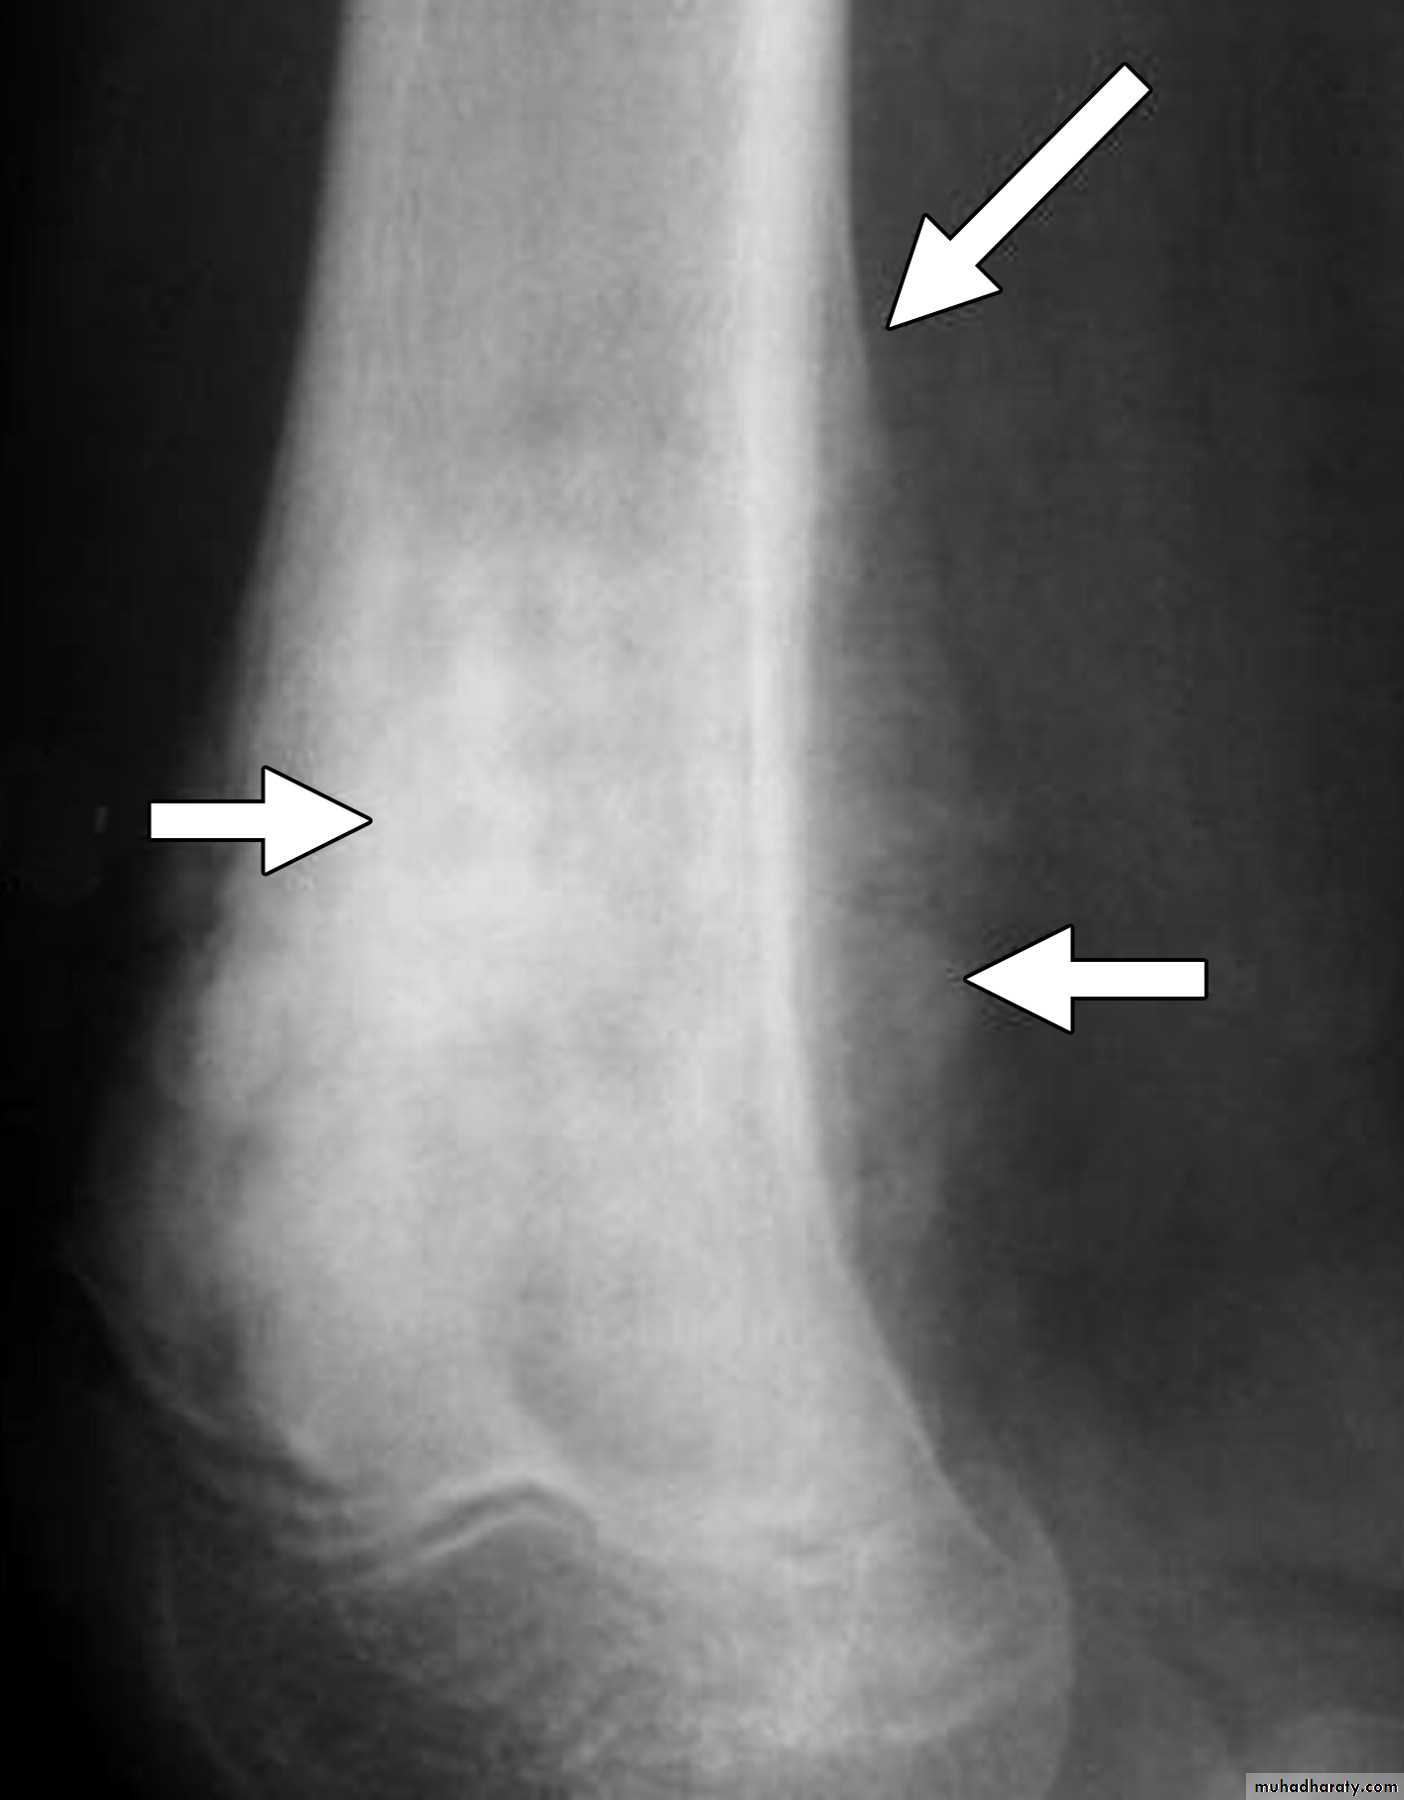

1.Zone of transition

2.The adjacent cortex

3.Expansion

4.Periosteal reaction